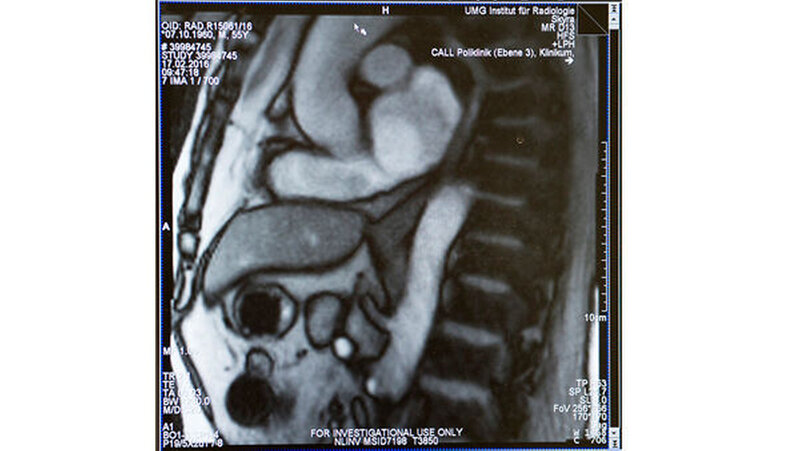

Ein interdisziplinäres Ärzteteam der Universitätsmedizin Göttingen und Forscher des Max-Planck-Instituts für biophysikalische Chemie, Göttingen, haben erstmals den Vorgang des Schluckens mithilfe bildgebender Verfahren dargestellt. Das Forscherteam nutzt dafür das Verfahren der Magnetresonanz-Tomografie (MRT) in Echtzeit. Mit dieser „Echtzeit-MRT“, kann der Schluckakt mit 25 Bildern pro Sekunde dokumentiert und untersucht werden.

Das Echtzeit-MRT liefert Bilder, die für diagnostische Zwecke in der Klinik und für die Behandlung nutzbar sind. Ursachen von Sodbrennen oder Schluckstörungen lassen sich genauer erkennen und untersuchen. Für eine individuelle und gezielte Behandlung der Volkskrankheit Sodbrennen eröffnen sich damit neue Wege.

Die Untersuchung wurde an 24 Patienten durchgeführt.